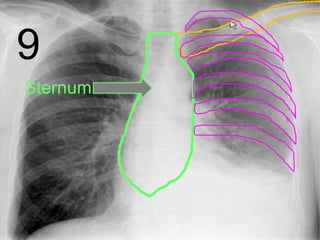

Sternum

Clavicle

9

Ribs